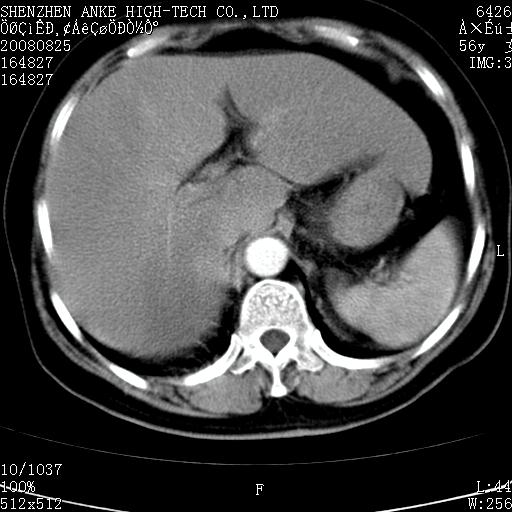

患者,女性,56岁,腰痛3年,查:右腹部约8x10cm肿块,固定,无压痛;8月23日在外院做了平扫,发现右肾巨大肿块(外院具体诊断不祥);今天在我院做了静脉肾盂造影,示:右肾明显增大,分泌功能明显减弱。

1)考虑右肾癌并右肾静脉瘤栓形成。2)脂肪肝。